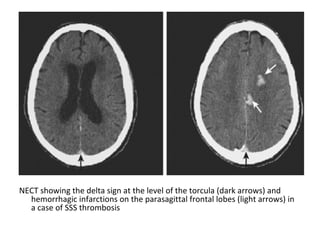

NECT showing the delta sign at the level of the torcula (dark arrows) and

hemorrhagic infarctions on the parasagittal frontal lobes (light arrows) in

a case of SSS thrombosis